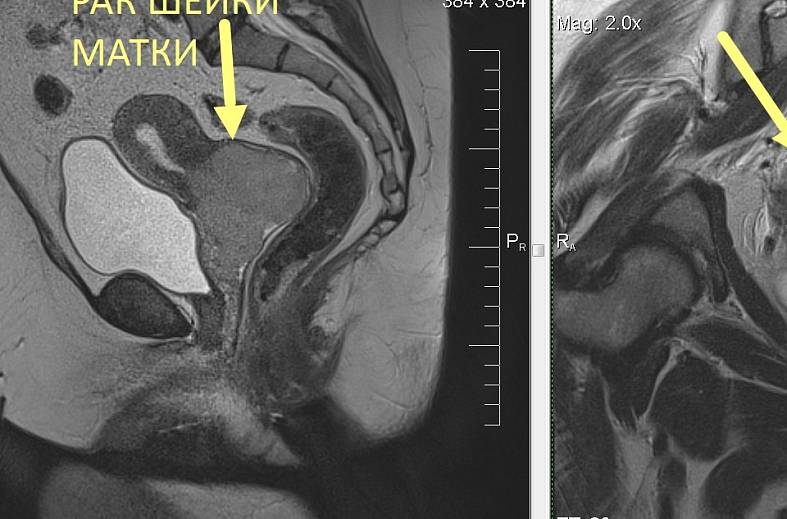

КТ ретроперитонеального фиброза: Изображения и диагностика